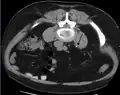

Three-dimensional reconstructed CT scan image of a ureteral stent in the left kidney (indicated by yellow arrow), with a kidney stone in the inferior renal pelvis (highest red arrow) and one in the ureter beside the stent (lower red arrow)

A kidney stone at the tip of an ultrasonic stone disintegration apparatus